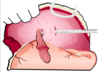

Incisional gastropexy procedure

incise the _seromuscular_ layer in gastric antrum and right abdominal wall- dont penetrate mucosa suture edge of abdominal wall to gastric incision w/ simple continuous pattern **3**-4cm oral to pylorus in the _transverse abdominus_ make the incisions so that pyloric outflow tract and proximal duodenum are not twisted or kinked